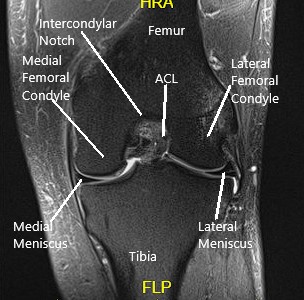

El examen de resonancia magnética de la rodilla izquierda sugirió un

desgarro complejo del asta posterior del menisco medial

. Pequeño desgarro de escisión horizontal del cuerpo del menisco lateral. Derrame articular moderado con sinovitis.

Resonancia magnética de la rodilla en la sección sagital y coronal.